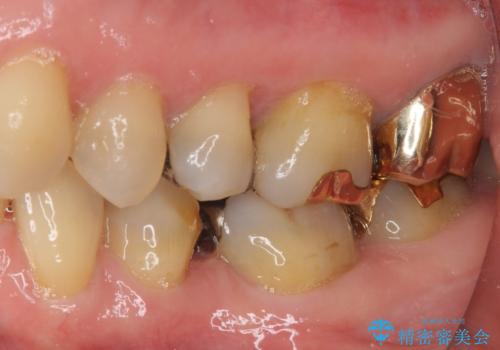

外れてしまった銀歯 セラミックインレーで自然な仕上がりに

- 奥歯の銀歯が外れてしまったため、セラミック治療を希望された患者様です。

セラミックインレーによる修復治療を実施しました。

正面から見える場所であったため、セラミックインレーで自然な口元にすることができました。